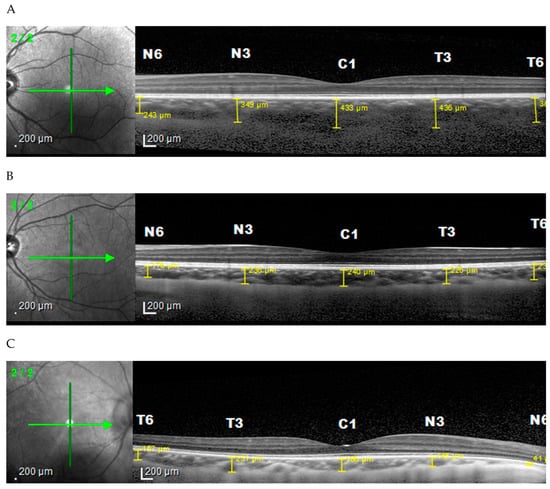

2. Materials and Methods

2.2. Ophthalmology Examination